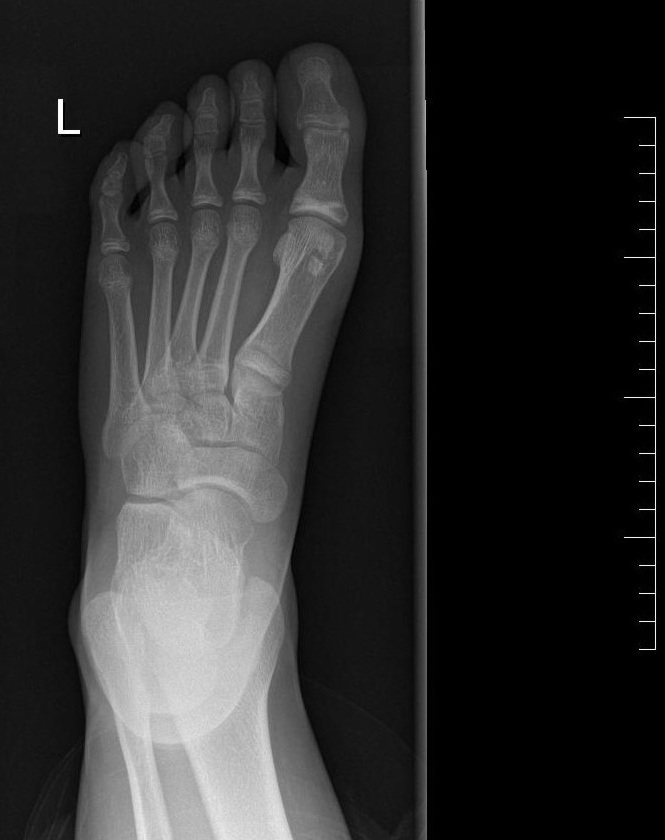

Paciente de 11 años que acude a Urgencias por dolor en el pie izquierdo de 6 meses de evolución, junto con inflamación de este en las últimas 24 horas. No guarda relación con traumatismo ni con sobreesfuerzo físico. A la exploración física, presenta dolor a la palpación en la articulación metatarsofalángica del primer dedo, con movilidad conservada. Se realiza radiografía de la extremidad (Figuras 1 y 2).

Figura 1. Radiografía ósea anteroposterior del pie izquierdo. A nivel de cabeza del primer metatarsiano, se objetivan tres formaciones de densidad cálcica de márgenes regulares, bien delimitados, no escleróticos.